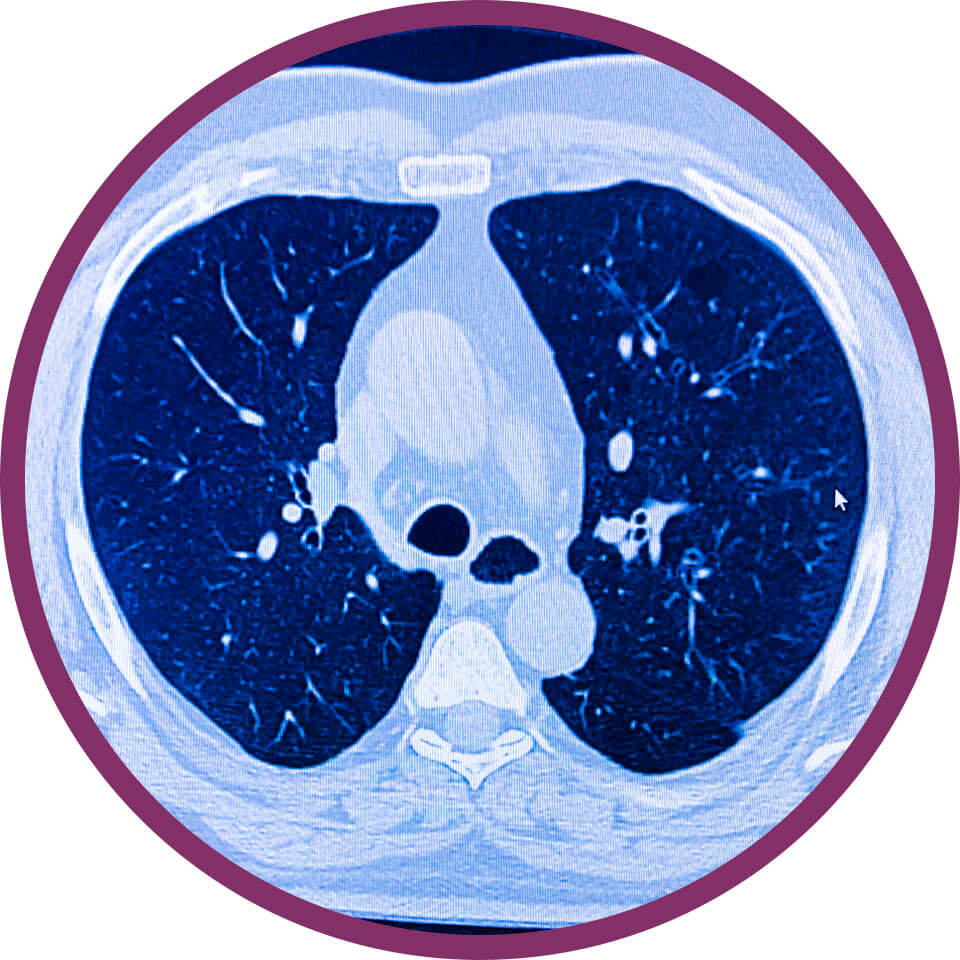

Tüdő CT

Tüdő CT

Hogyan végezzük a vizsgálatot?

A CT-készülékünk egy nagy, vastag gyűrűhöz hasonlít, melynek aljában egy asztal van, ami mozog. Ön ezen az asztalon fekszik mozdulatlanul, miközben a felvételeket készítünk. A vizsgálószerkezet működése közben zúgó, búgó hangot ad ki, de ettől nem kell megijedni, hisz a vizsgálat fájdalommentes. A vizsgálat közben Ön folyamatosan audiovizuális kapcsolatban van az operátorral.

Miért válassza ezt a vizsgálatot?

A kontrasztanyag adásával kombinált mellkas CT vizsgálat elvégzése elsősorban tüdőembólia gyanúja esetén, illetve korábban igazolt tüdőgóc, krónikus gyulladás, kerekárnyék vagy daganat gyanúja esetén indokolt, az elváltozás természetének és a nyirokcsomó érintettség megítélése céljából!

Mikor nem végezhető el a vizsgálat?

A CT vizsgálat röntgensugarakkal történik, ezért terhesség illetve szoptatás ideje alatt nem ajánlott. Kiskorú/gyermek esetében nyomós indikációval vagy szakorvosi beutalóval végezhető el a vizsgálat. Kontrasztanyag adása kerülendő kontrasztanyag érzékenység, súlyosan beszűkült veseműködés esetén és cukorbetegségben alkalmazott metformin tartalmú gyógyszerek szedése esetén.